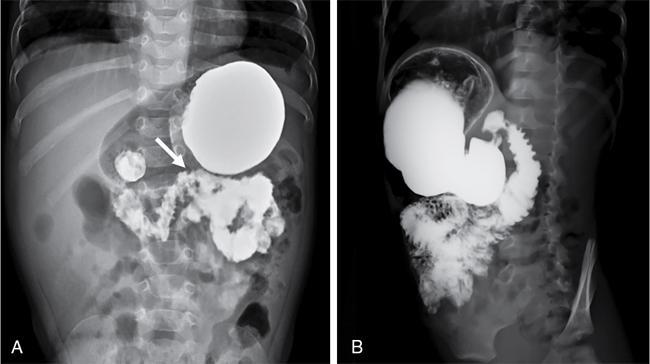

S. Muralinath, C.V. Kanimozhi, Krishnarjun M The focus and ambit of this chapter are restricted to the oesophagus as a subsequent author is dealing with the upper GI tract. Hence the narrative is confined to common problems like GER/GERD, achalasia, hiatus hernia, corrosive injury and ingested foreign bodies seen typically in infants and young children. The oesophagus is actually an anatomic and functioned continuum that serves essentially as a conduit between the hypopharynx and stomach. One cannot study the oesophagus in isolation without basic knowledge of the preceding structures and the following organs. Hence a brief consideration of the same is done along with the study of the oesophagus. The oesophagus basically transports the oropharyngeal contents onto the stomach. It goes without saying that there is bound to be an overlap or spillover of the proximal oropharyngeal and distal gastric disease onto the oesophagus. Dysphagia could be oropharyngeal or oesophageal and vomiting or regurgitation could be oesophageal or gastric. Hence the discussion will consider relevant proximal and distal elements in brief. Radiology and imaging play a significant role in the evaluation of children with upper GI tract diseases and is one of the most important sources of information for the clinician in the evaluation of GI tract diseases. The history and physical examination are crucial, but imaging plays a vital role in the assessment of GI tract disease. A plethora of investigative modalities are at one’s disposal today; hence, a good rapport between the clinician and the radiologist is essential in choosing the right investigations. Despite the advances in imaging technology and sophistry in techniques, the vast majority of the upper GI tract diseases in children, thankfully require only a few basic studies – conventional radiology (plain X-rays, fluoroscopy and contrast studies) and ultrasound. The downside is that in paediatric practice, these studies require in abundance practice and skill. Radiographic and fluoroscopic examinations are the mainstay in the study of upper GI tract disease in children. A preliminary plain film is the usual starting point; this supplemented by a few simple contrast studies and ultrasonography is all that is needed in the evaluation of most of the common upper GI tract diseases in children. It is mandatory that upper GI tract studies be done under fluoroscopic monitoring, as vital information is gained through the dynamics observed and the study is actively monitored and tailored to suit the clinical need. Barium is still the most commonly used contrast medium. Water-soluble contrast media are considered in specific circumstances as they are of value when the possibility of extravasation or perforation exists – for example, post-op evaluation of TEF repair. In the study of the oesophagus, hyperosmolar (ionic) contrast media are seldom utilized, as they may cause pulmonary oedema in the event of an aspiration. Nonionic low osmolar contrast media are preferred; especially in the newborn and young infant, because of the impact of ionic hyperosmolar contrast media on the water electrolyte equilibrium. To recognize the abnormal one has to realize the normal. The oesophagus is a relatively straight, hollow tube that follows the contour of the spine from the hypopharynx in the neck to the stomach in the abdomen. It has a relatively short cervical and abdominal segment with a long intervening thoracic component. It is governed at either end by high pressure zones. The upper oesophageal sphincter (UES) is defined by the cricopharyngeus, whereas the lower oesophageal sphincter (LES) is a poorly defined anatomic zone that is at and above the oesophago-gastric junction, partly straddling the diaphragmatic hiatus. The oesophagus has an inner mucosal layer lined mainly with stratified squamous epithelium which has negligible secretory and absorptive function. The outer muscular component has an external layer of longitudinal fibres and an internal layer of circular fibres. The musculature of the upper third is striated, whereas, in the lower third, it is nonstriated smooth muscle. The intervening segment is one of transition from the striated to the nonstriated. This nature of muscle distribution accounts for the central nervous system disorders affecting the motility of the pharynx and upper oesophagus, whereas autonomic system dysfunction leads to affliction of the lower oesophagus and the oesophago-gastric junction. The oesophagus at rest is in a collapsed state, bound at either ends by the UES and LES, respectively. These physiologic sphincter mechanisms maintain a tonic squeeze at rest generating a high pressure zone that prevents retrograde flow of contents from the oesophagus or the stomach. The function of the oesophagus is to propel contents from the pharynx onto the stomach. This is achieved through the mechanism of peristalsis. The pacemaker for the aboral, primary peristalsis is the act of deglutition. This once initiated travels down to the stomach. Peristalsis consists of a circular constrictive wave preceded by a wave of relaxation. This complex motor sequence is the result of the exquisite and intricate neural circuit (Auerbachian and Meissner plexuses) performing flawlessly in the gut wall. This wave drives the content in an aboral direction. While primary peristalsis is initiated by the act of swallowing, secondary peristalsis occurs in response to local oesophageal stimulus, the primary one being distention. This compliments the primary peristalsis in clearing the content. These propulsive mechanisms make sure that nothing stays in the oesophageal lumen, thus preventing stasis and its attendant complications. At rest, oesophagus is always kept in a collapsed state with no contents. Diagnostic tests commonly used in the evaluation of the oesophagus are oesophagogram, endoscopy and manometry. Endoscopy is for evaluating the oesophageal morphology, especially that of the lumen and the mucosa. Manometry offers information regarding the motor function; whereas an oesophagography provides information regarding both morphology and motor function and is usually the initial study in the evaluation of oesophagus. Barium is still the preferred contrast medium as it has the ability to provide a superior mucosal coating than any other contrast media. This coupled with its inherent density offers excellent contrast and detail. Barium is an inert substance with no adverse effect in the GI tract but that is not so when it leaks out and barium peritonitis is a much dreaded event. Water soluble low osmolar nonionic contrast media are considered when barium is contraindicated as in perforation. Water soluble hyperosmolar ionic contrast media are seldom used in paediatric practice as they cause airway and pulmonary compromise in the event of an aspiration. In newborn and young infants it can have a significant adverse effect on the water electrolyte equilibrium. The sole exception could be as therapeutic enema in meconium related disorders. Generally in paediatric practice a contrast swallow is seldom done in isolation. It is always a component of the upper GI series. The study is mostly done to evaluate vomiting or dysphagia. The problem could be in the oesophagus or elsewhere, for dysphagia could be pre-oesophageal and vomiting could be post-oesophageal. Contrast swallow may be done in isolation on follow-up studies, such as in post corrosive stricture, when the pathology has been localized, to evaluate the outcome of management. Be it a contrast swallow or an upper GI study, fluoroscopy is mandatory. Basic fluoroscopy and radiographic examination is the bedrock, when it comes to imaging evaluation of the oesophagus. An oesophagogram, as is the norm is done in conjunction with the upper GI series; wherein the mechanism of swallowing, the dynamics of peristaltic transit of content through oesophagus, stomach, duodenum and the proximal small bowel is studied along with it is morphology. Evaluation of the duodenum and DJ flexure is crucial for the documentation or exclusion of the rotational anomalies of the gut (Fig. 7.9.1). A standard operating protocol in a paediatric radiography suite would be: In children, especially the young ones, the oesophagus is a relatively simple structure and the mucosal folds are not that evident as in adults during a contrast swallow. But one can see often the extraneous impression caused by the aortic arch, the left main bronchus and the normal left atrium (Fig. 7.9.2). Normal peristalsis can be observed with the constricting ring preceded by the wave of relaxation leading to the aboral transmission of contrast. The peristalsis though, may not be as vigorous as in grownups. A word of caution during fluoroscopy – in the newborn and young infants the mediastinum and its structures are quite flexible and the oesophagus rather pliant. This will result in a peculiar configuration of the oesophagus during respiration. This is especially so if the infant cries leading to a bizarre and tortuous appearance of the oesophagus. To begin with this may be startling, but the entire process will settle once the crying induced Valsalva and the resultant elevation of intra-thoracic pressure eases. For the uninitiated a static film taken without fluoroscopy will be bewildering when viewed. Remember fluoroscopy is a must in paediatric upper GI study. A point to note is, small amounts of air in the oesophagus is not an uncommon finding in infants as they are quite aerophagic while feeding or even otherwise. Gastrooesophageal reflux (GER), hiatus hernia and achalasia cardia are considered in continuum as they essentially represent altered states at the same anatomic site – the oesophago-gastric junction. The literature on the anatomy and the physiology of the oesophagogastric junction is quite exhaustive; despite the various and numerous studies, the normal function of this junction defies clarity. GER as the name implies is the passage of gastric contents across the gastro-oesophageal junction into the oesophagus. The precise mechanism by which, aboral, unidirectional transit of content occurs at the oesophago-gastric junction is still not clearly understood. Various factors and mechanism are said to play a part in the valve like function of the oesophago-gastric junction. Apparently, the most important factor is the high pressure zone in the lower oesophagus representing the LES. A segmental tonic mechanism is considered to be operative in maintaining the high pressure. The other contributory factors said to assist mechanically are, the pinch-cock effect of the decussating crural fibres of the diaphragm, the unique anatomy of the junction providing the angle of His, the mucosal flap-valve mechanism, the posterolateral location of the fundus and the length of the intra-abdominal oesophagus. Transient relaxation of the LES is considered to be the primary mechanism by which reflux is said to occur. An autonomic, vagus mediated reflex regulates the transient relaxation of the LES. This relaxation reflex can be initiated by gastric-distention or by the initiation of swallow even when not leading to oesophageal peristalsis. The diagnosis of GER is made on a clinical basis from the history and physical examination. GER in a healthy, thriving infant is a physiologic and self-limiting entity. It is mostly managed by empirical and conservative measures along with parental reassurance. It is essential to differentiate physiologic GER from the pathologic state – GER disease (GERD). In GERD, as the name implies, the infant or child is no longer at ease. When GER is frequent and persistent leading to troublesome symptoms or complications, then what you have at hand is GERD. GER can have GI symptoms as well as non-GI related symptoms, like the oft stated peculiar manifestation of neck contortions in Sandifer’s syndrome. Reflux of acid content on to the airway may cause apnoea, cyanotic spells and the much dreaded sudden infant death syndrome. Another subset is there with silent or occult GER. In these infants or children, the GER does not manifest as regurgitation, vomiting or rumination. It is because these reflux does not quite reach the oral cavity to manifest as symptoms and yet could potentially be as harmful. Hence investigation is done to evaluate occult GERD and in high risk groups (neurological disorders, trisomy 21 and chronic respiratory ailments as in cystic fibrosis) suspected to have silent GER. An ideal oesophageal test should detect GER, establish a causal relationship between the event and disease, provide information about the nature and extent of reflux, detect the pathologic changes wrought by the disease and establish a differential diagnosis if any. This is a tall order and as expected no single test can provide all the information. Hence the tests need to be done in a judicious manner depending on the information required. This study has been the traditional choice; but it has several limitations. It lacks sensitivity and specificity. GER is a 24 hours diurnal event and any study that focuses on a brief period of time is certainly at a loss. As yet there is no universally standardized technique. Ideally the study should be done on a relatively relaxed and comfortably restrained supine infant. The infant is fed barium through a feeder with the head end slightly elevated. Adequate barium, comparable to a normal feed volume is ingested to fill the stomach. The infant should be supine now. During this period, judicious, intermittent fluoroscopy is utilized to observe the dynamics of swallowing, oesophageal transit and once the stomach is adequately full, for the occurrence of reflux (Fig. 7.9.3). Provocative measures to elicit reflux is best avoided as they do not represent a physiologic event. Clear fluid or water may be given to washout the oesophagus when needed, and to look for GER; as this can be considered to simulate a life event. Once that is done, passage of barium from the stomach to the proximal small bowel is observed. This is done to evaluate the duodenal ‘C’ loop and the DJ flexure to exclude malrotation and other obstructive pathologies. The study has to be as brief as possible as one is dealing with ionizing radiation. The upper GI series is not for just documenting GER but done to evaluate other causes of vomiting as it provides excellent anatomic information along with motor function.